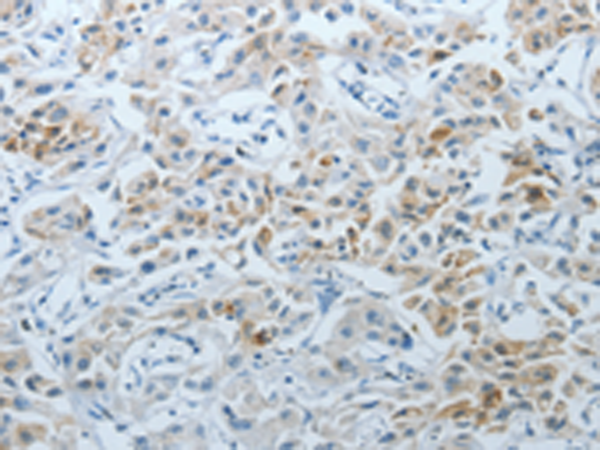

分类: 科研抗体货号: P00547别名: MUC-20应用: IHC反应种属: Human